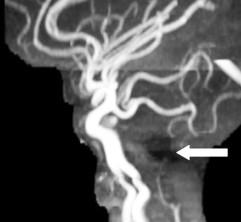

White arrows: Small pons remnant with nonformation of the midportion of the brainstem

Abnormal vertebrobasilar vasculature

Etiology?

very early vascular insult?

No gliosis to suggest hypoxia or ischemia

In animals: seen with hox gene deletions leading to lack of single rhombomere development, so brainstem “short” but typically not fully disconnected